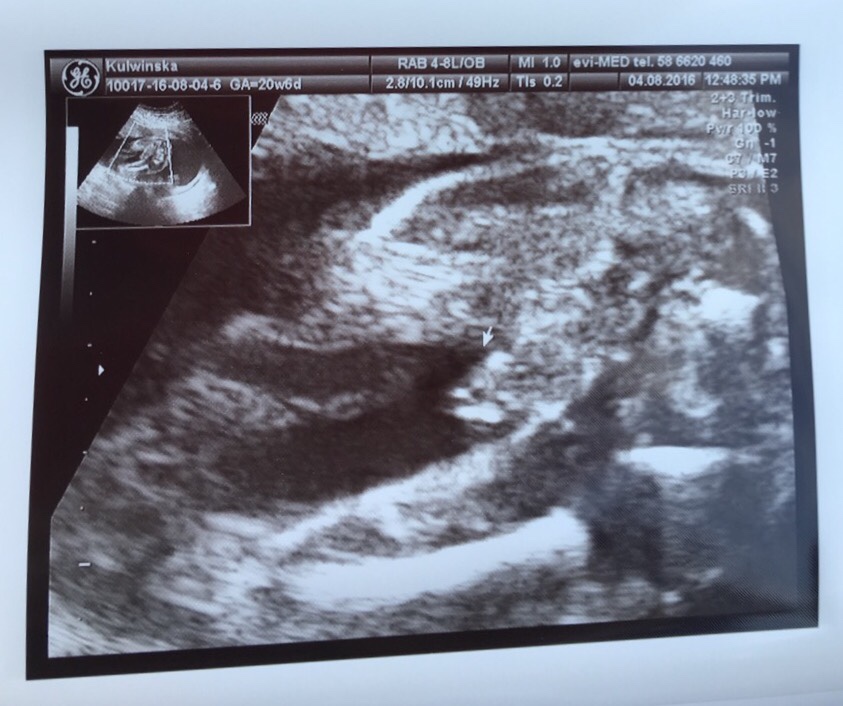

No i ja po juz...pół kilo zdrowego syna!!![emoji170][emoji170][emoji170][emoji7][emoji7][emoji7][emoji7]

Lekarz już zaznaczył, że łatwo nie bedzie, bo na bank rośnie pod 4 kg...![]()